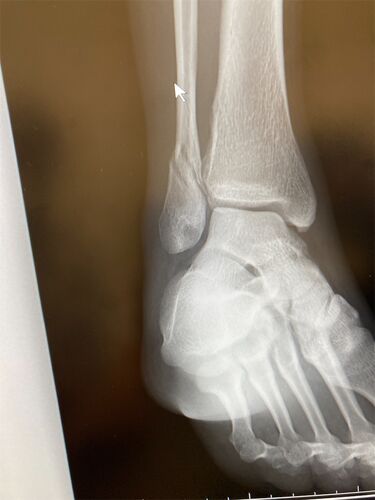

人生初骨折からの入院からの手術

こんにちは、MASAKIです。 4/30にタマダサーキットで練習した日に最終コーナー転けてピットレーンのスポンジバリアに突っ込んで骨折した、、、、笑 その日は痛みはあったけど大丈夫だろ〜と思ってそのまま家に送ってもらい 次の日もけんけんしながら生活して…